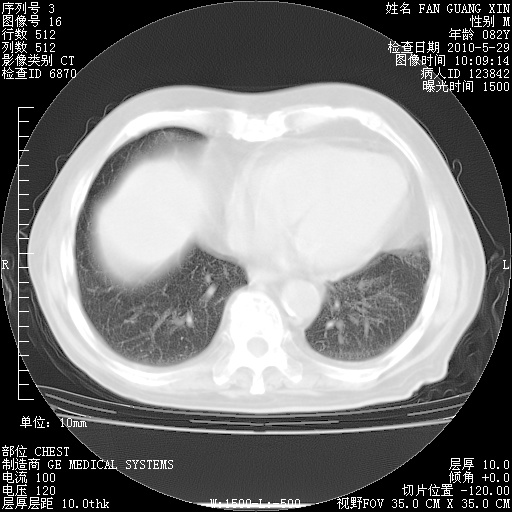

再治疗10天后的肺部CT

再治疗10天后的肺部CT 纵膈窗

阅读此次胸部CT,肺间质渗出性改变较入院时有吸收。目前从体温、白细胞、中性分叶明显增高,肯定存在细菌感染(发生医院感染哦,若无消化道及泌尿系统等感染的依据,肺部感染可能大)。若你院头孢哌酮舒巴坦钠耐药率较高,同意你的方案,若48小时体温仍高,可考虑使用碳青霉稀类抗菌药物,同时可予超声雾化、注意滴数时加大液体量。白蛋白33.30g/L较低哦,需加强营养等支持治疗。